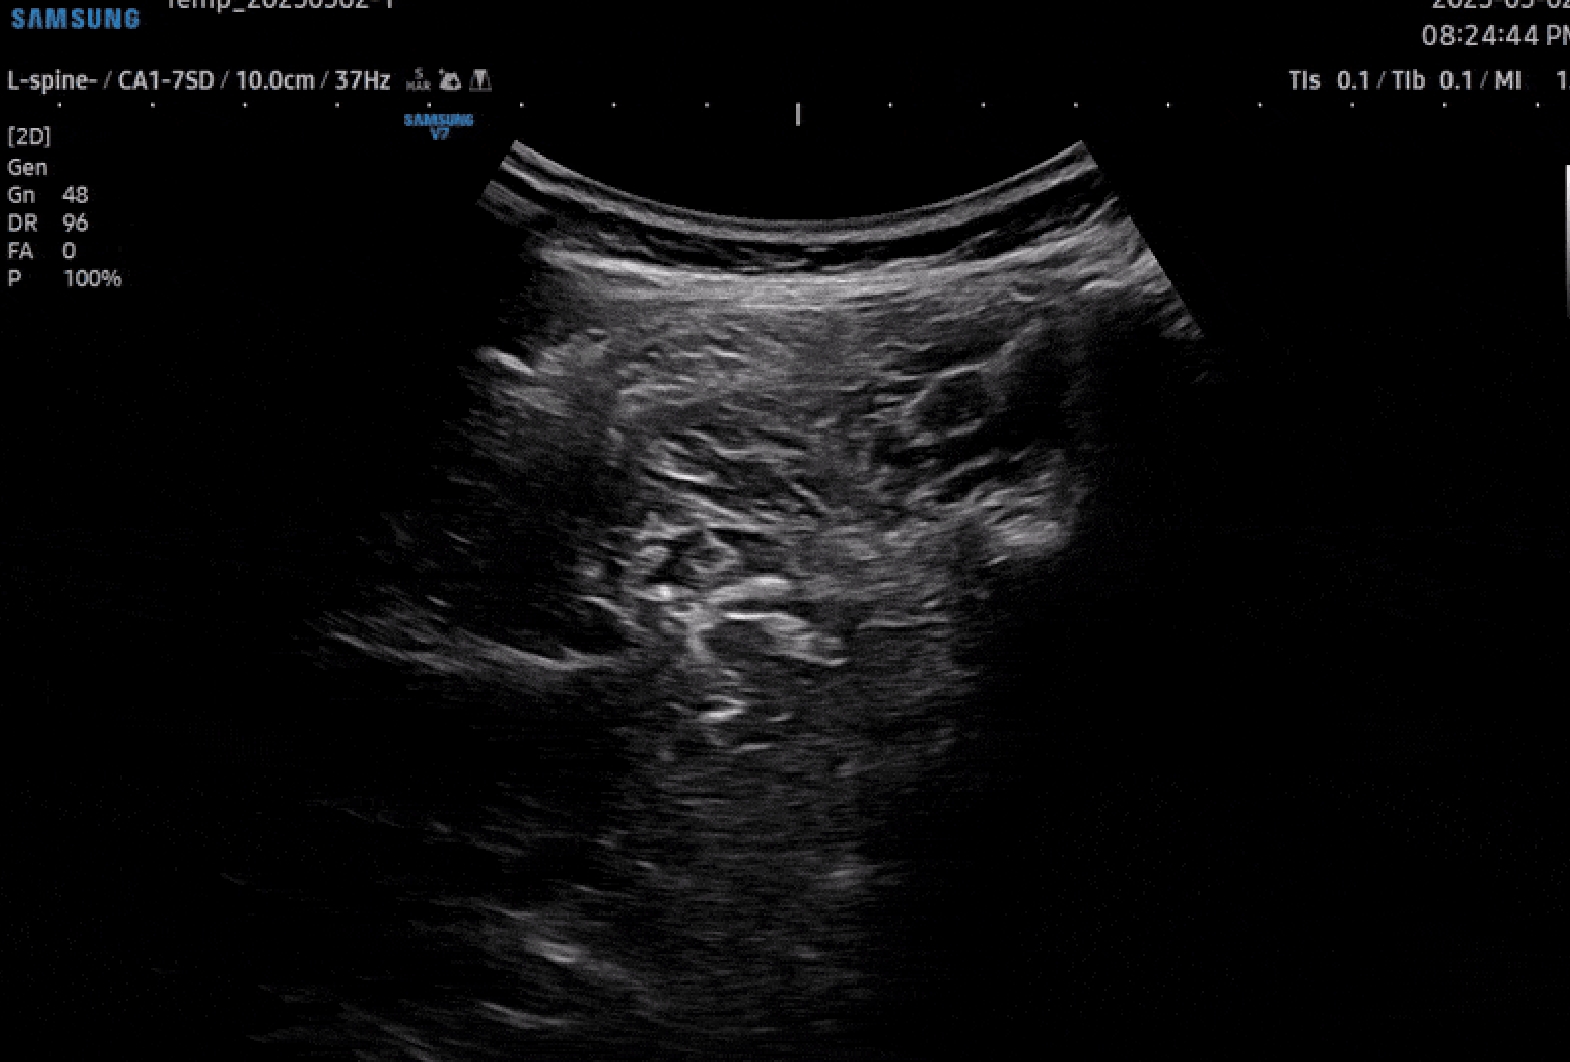

고해상도 초음파 검사를 통해

통증의 원인을 확인하고

손상된 조직 상태를 정밀하게 확인합니다.

손상된 연부조직, 근육, 힘줄, 인대 상태를

유심히 관찰하여 통증의 근본 원인을 정확하게

초음파로 진단이 가능합니다.

비침습적 검사 과정

정교한 타겟 치료

방사선 노출 걱정 없는 안전성